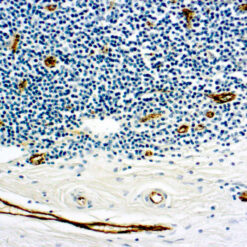

| Positive Control Tissue | Testis |